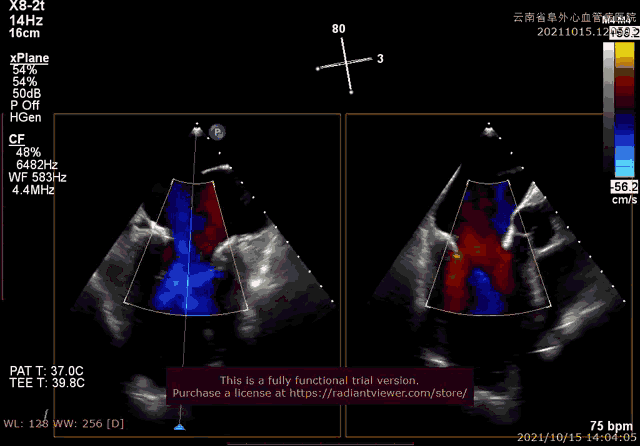

经过云南阜外医院结构性心脏病MDT团队综合讨论评估该患者病情后,患者为传统手术高危患者,瓣膜病变解剖无法行介入修复,决定进行MitraFix™经心尖二尖瓣植入。术前心脏CTA二尖瓣D形瓣环面积折算直径34mm, 模拟植入34号介入二尖瓣膜(外经约40mm)后左心室NeoLOVT面积可(>150mm2)。手术在单纯超声引导下完成,采用左侧肋间4cm微创切口心尖入路,在超声引导下,输送系统准确跨瓣,并将瓣膜准确释放于二尖瓣瓣瓣环,瓣膜释放后支架贴合牢固,无瓣周漏及瓣内反流,二尖瓣前向血流通畅,平均压力阶差2mmHg,左心室流出道通畅,流出到血流速度为2.3m/s,平均压力阶差8mmHg(图2-3,视频1)。顺利撤出输送系统,关闭心尖切口,手术顺利结束。

图3:采用3D实施多平面定位引导瓣膜释放